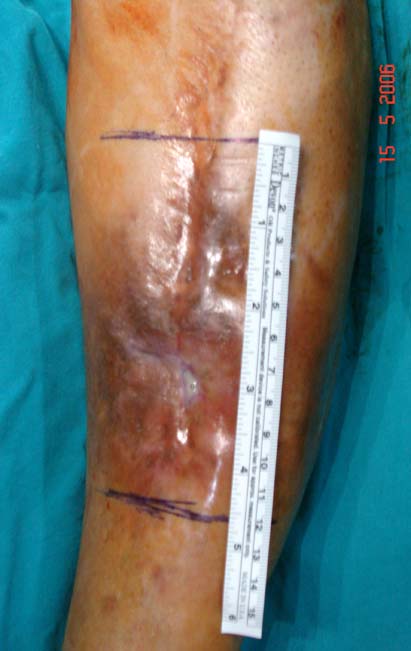

Chronic osteomyelitis leads to necrosis of bone and soft tissues. Dead bone is a nidus which hosts pathogenous microorganisms. Defence mechanisms of the host is usually not in optimum condition to deal with microorganisms. Antibiotics can’t reach the infection site because blood flow is disrupted. For these reasons, dead bone has to be completely removed by radical debridement.

Appropriate radical debridement necessitates excision of all necrotic bone and soft tissues, and frequently causes instability at the involved extremity. The remaining bone and soft tissue defect has to be fixed and reconstructed. The distraction osteogenesis method of Ilizarov is used successfully for achievement of union, correction of the deformity, elimination of limb length inequality and reconstruction of segmental bone defects.